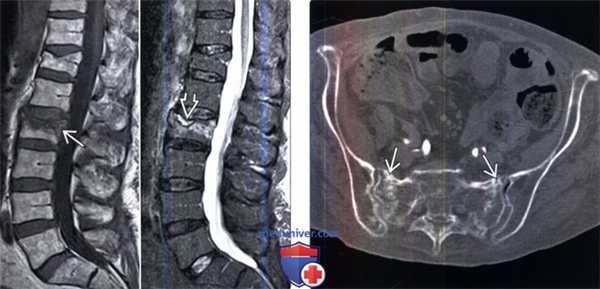

(Слева) Сагиттальный срез, Т1-ВИ: гипоинтенсивность сигнала, ориентированная параллельно замы-кательной пластинке. На сагиттальном STIR МР-И отмечается гиперинтенсивность сигнала в этой же области и симптом жидкости. Симптом жидкости чаще наблюдается при свежих доброкачественных остеопоротических переломах. Остеопороз и минимальная травма приводят к остеонекрозу в области поврежденной замыкательной пластинки. В зону остеонекроза «продавливается» жидкость, что становится причиной появления МР-симптома «жидкости».

(Справа) Аксиальный КТ -срез: признаки двустороннего остеопоротического перелома крестца. У 2/3 пациентов в таких случаях не удается установить факта травмы либо травма эта оказывается минимальной.